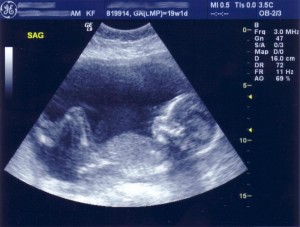

وأجرى الباحثون دراستهم على 1.4 مليون طفل في ولاية فلوريدا الأمريكية، وراجعوا سجلاتهم ووجدوا أنهم ولدوا جميعاً بين الأسبوعين 37 و 41 من الحمل، وكان ذلك بين عامي 1994 و 2002.

وبحسب تقدرات الأطباء، فإن الولادة الطبيعية تكون فى الأسبوع 37 من الحمل، وما بعد ذلك يعتبر ولادة متأخرة.